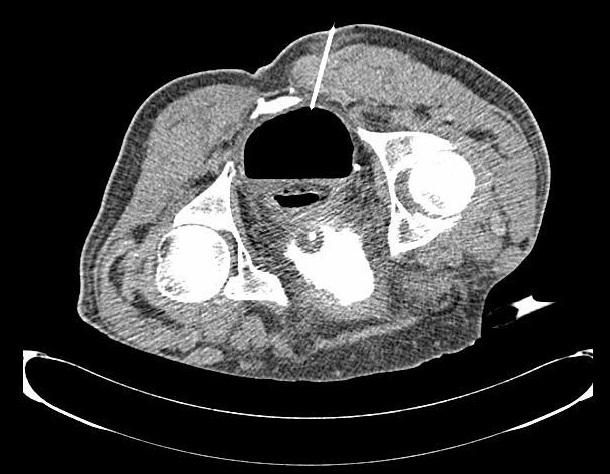

经臀-需要在骶棘韧带以上入路(高位经臀穿刺) High Transgluteal Drainage

高位经臀穿刺,需要在知情同意书上专门强调出血和针道疼痛的副作用较通常高

扫描架倾斜,扫描安全的进针途径 ![]() 经阴道(Transvaginal) 经会阴和经直肠穿刺通常也被成为经内腔(transendocavitory)穿刺引流。经阴道对盆腔脓肿进行手术引流是一种较成熟的方法,具有确定的益处,但大多数情况下,积液都使阴道壁移位,使这条通路的应用受到限制。可以在超声引导下进行引流,这样可以准确地将针头或导管放入积液内,这个积液的位置可以毗邻阴道穹窿,但没有使之变形。